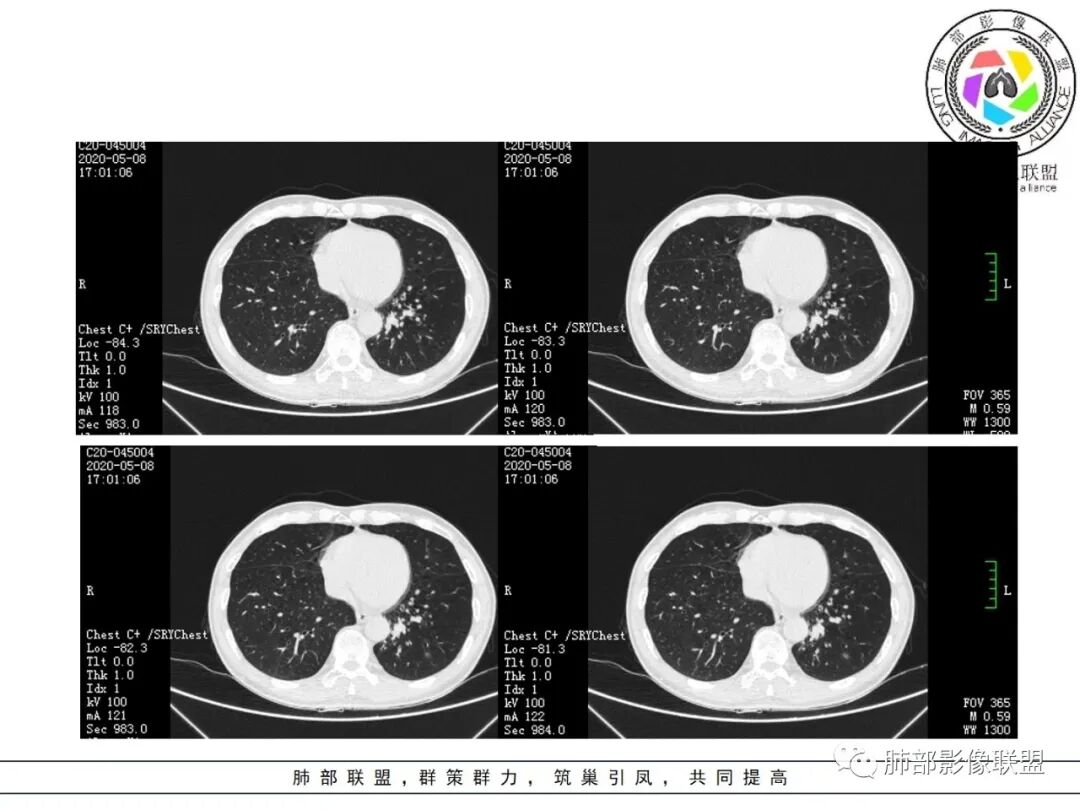

大雄:抗感染不吸收还是要警惕癌尤其主动脉旁的病灶红星:老年患者,咳嗽咳痰两个月,既往有糖尿病病史10年,左肺下叶后基底段斑片状、条索状、斑点状多形态的病灶,病灶内可见支气管征以及狭窄扩张的支气管影像。重建图像上可见到病灶沿支气管爬行。增强扫描病灶轻度强化,临近胸膜增厚。首先考虑感染性的病变,结核性的可能性最大。鉴别诊断上注意排除肺克以及淋巴瘤。三个石头:左肺下叶多发斑片,结节,条索,多态性?结核?多个结节边缘长毛刺,胸膜牵拉,分叶。矢状位支气管走行扭曲,没有完全阻塞,应该有粘液栓,有点像指状。主动脉旁病灶边缘平直,部分有鹏隆感,延迟强化。抗炎病灶变化不明显,结核?真菌?肿瘤也除外不了。没意见:左肺下叶基底段结节,膨隆、深分叶,毛刺,内侧串珠结节,中轴间质增厚,管腔狭窄,后基底段亚支不张,强化情况不明,考虑恶性,腺癌可能性大,另指套样征像,支气管壁增厚,不除外霉菌感染流心明智:老年患者,咳嗽咳痰2月。既往糖尿病史10年。胸CT:左肺下叶基底段多发结节影、斑片影、条索影,多数结节影沿支气管血管束分布,支气管壁厚,部分结节分叶、指状突,后基底段支气管狭窄闭塞。重建可见到病灶沿支气管爬行。增强扫描病灶明显强化,部分斑片影内可见低密度灶。普通抗感染无效。考虑:恶性病变,鳞?小?鉴别TB、隐球等。王秀仙:左肺下叶沿支气管血管束分布斑片、结节影,部分呈管状铸型生长,管腔狭窄,后基底段支气管阻塞,降主动脉旁不张实变,增强扫描病灶轻度强化,抗感染2周无吸收,考虑鳞癌。鉴别结核。蓝天白云:肺野内老年男性,咳嗽咳痰,有糖尿病病史,抗炎治疗无吸收。影像表现为左肺下叶支气管腔内结节影,支气管壁增厚,远侧小花小草,增强后实变影均匀强化,考虑鳞癌伴远端阻塞性炎症,鉴别结核。采莲:老年男性,咳嗽咳痰2月,有糖尿病史,左肺下叶沿支气管分布多发结节条状影,结节影不规则有分叶,成串珠样,靠下结节影成条索影,周围有空气储留,靠近主动脉不规则块状影,边缘平直,周围支气管壁增厚,支气管进入后阻塞,有糖尿病史,首选考虑炎性肺结核可能性大,鉴别肺鳞癌。了:左肺多发结节影,实性结节,,磨玻璃结节,左肺门结节影,深分叶,彭隆感,有血管滋养,考虑肿瘤,抗感染后病灶无吸收,感染不像,结节有强化,无卫星灶,结核可以排除不再涩的柠檬:老年男性,吸烟史,糖尿病史,咳嗽咳痰2月,抗感染2周无效。左下基底干及各分支管壁较弥漫增厚,伴支气管粘液栓,远端阻塞性肺炎,后基底段部分不张实变。先考虑感染病变,常规抗炎无效,需考虑结核、曲霉等,不能排除鳞癌合并感染,建议支气管镜检查。

影像所见:

结节伴分叶。

斑片影,考虑阻塞性炎症。

支气管壁厚,支气管腔内高密度影填充。

周围散在斑片影及结节影,类似“小花花草草”的感觉。

2.关于支气管:上述病灶辖区外侧段支气管截断,环壁结节,远端阻塞性肺炎,是肺癌的重要征象。